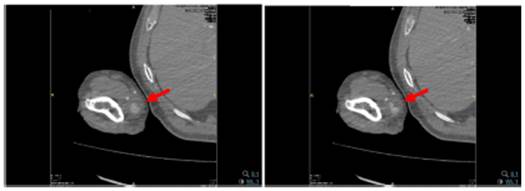

Se observa pseudoaneurisma de arteria cubital derecha de 22 x 21 mm de diámetro, con cuello de 2 mm (fig. 2).